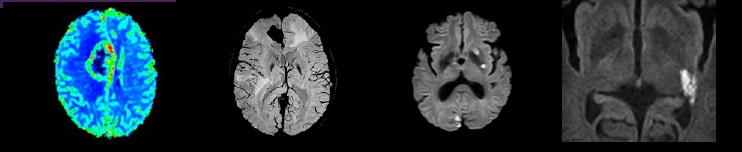

核磁共振:摇一摇再看

核磁共振机使用较强大的磁场,使人体中所有水分子磁场的磁力线方向一致,这时磁共振机的磁场突然消失,身体中水分子的磁力线方向,突然恢复到原来随意排列的状态。反复多次施加磁场又突然消失,核磁共振机会得到充分的数据并运算后成像。

简单说就相当于用手摇一摇,让水分子振动起来,再平静下来,感受一下里面的振动。所以,核磁共振(MRI)也被戏说为是摇摇看的检查。

02 MR(核磁共振)

MR(核磁共振)磁共振无电离辐射,拥有很高的组织分辨率,适于神经系统(脑、脊髓)、腹部(肝胆胰脾)、四肢关节软组织(半月板、韧带、肌肉病变、微小的骨折、骨肿瘤)、脊柱(椎间盘)、妇科肿瘤、头颈软组织等敏感度和特异度较高。磁共振血管成像对血管疾病的显示有独特优势。MR水成像对于诊断消化、泌尿系统疾病有很大价值。但磁共振对胸部疾病及钙化病灶显示不佳。

MR成像时间较长,噪音较大,一个部位至少需要近十分钟的检查时间,对于孩子的配合度要求较高,很多患儿经常因恐惧造成检查失败。对于不配合的儿童应使用镇静后检查,所以儿童磁共振检查应选择专门的儿童医院。